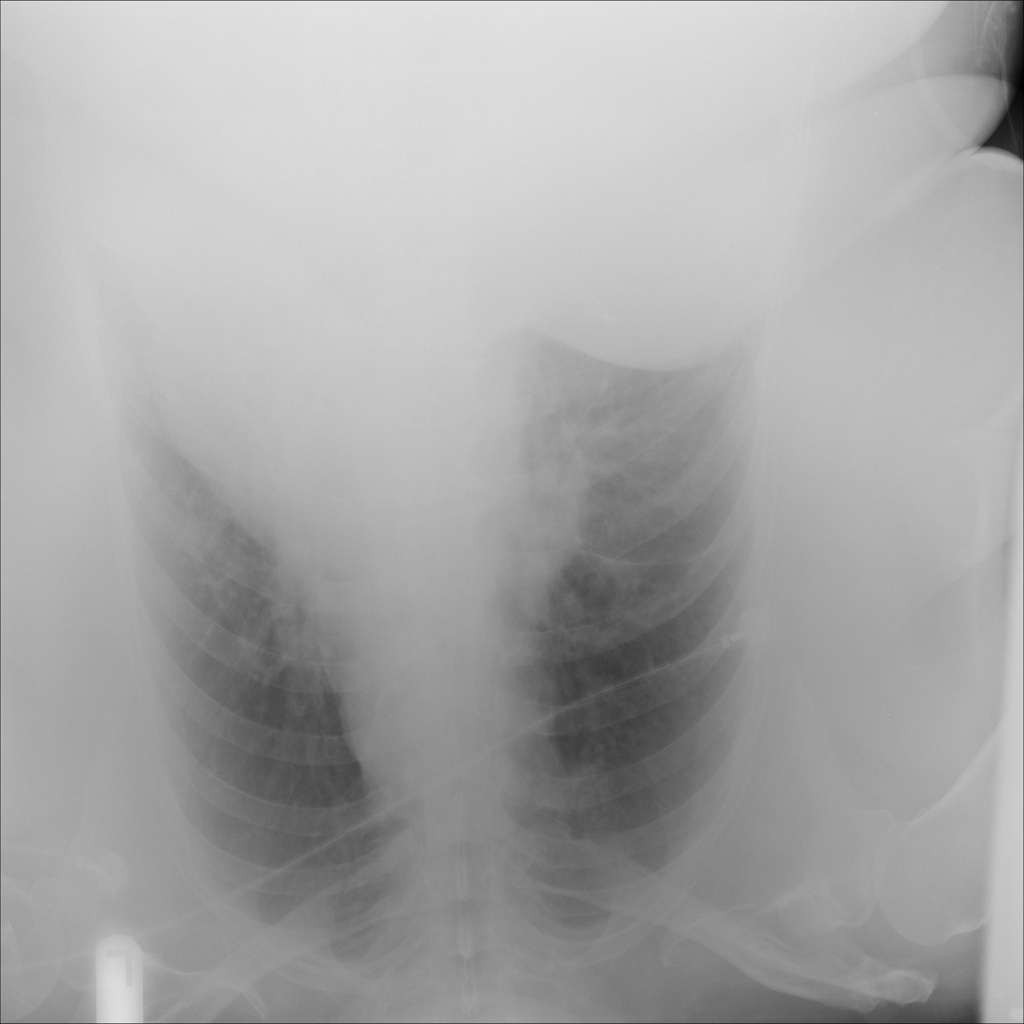

PAT-531A · IMG-006Consolidation

PAT-531A · IMG-006

PA